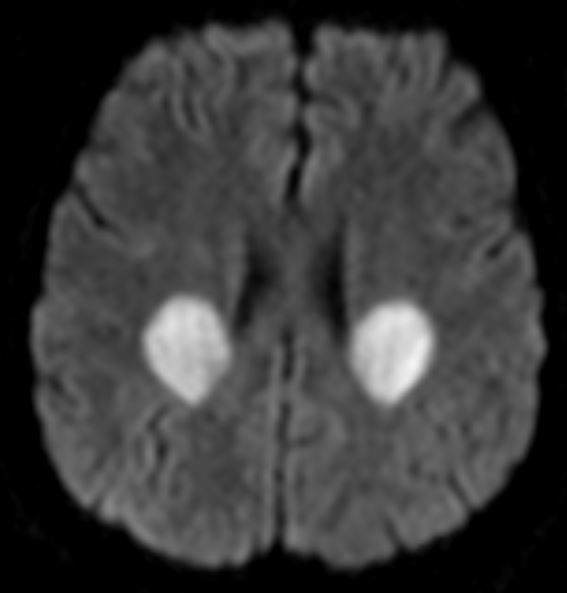

Tip of the day 💡: When the zone of acute ischemia does not respect vascular territories consider metabolic/mitochondrial strokes early. Note also the deep white matter lesions which are not acute.